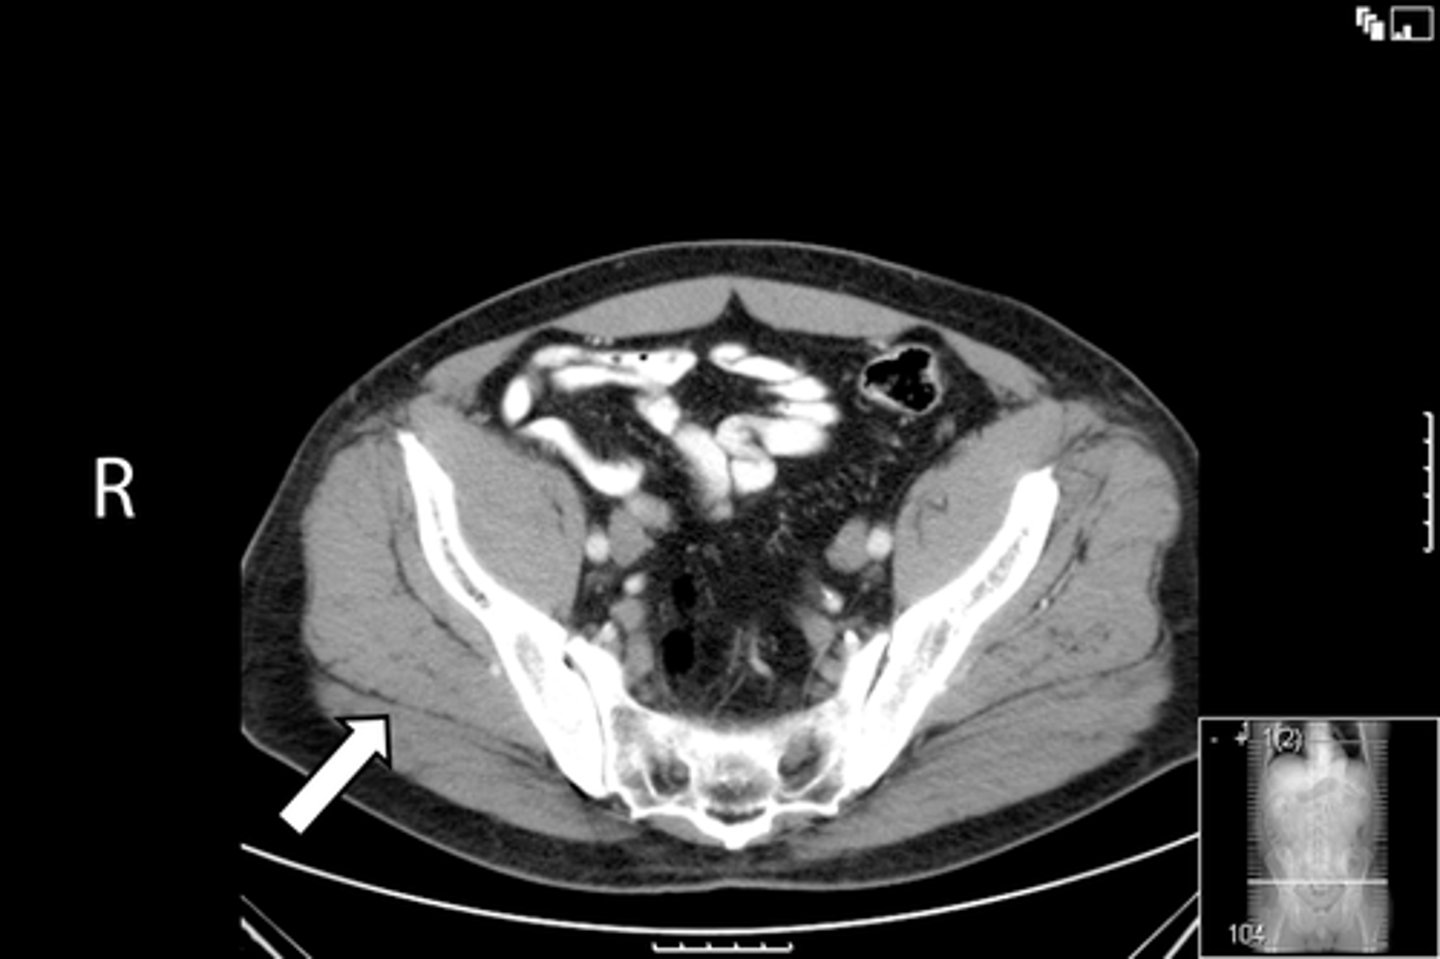

Axial bony pelvis CT

What is the image?

32

L ilium

<p>What is indicated in the image?</p>

New cards

What is indicated in the image?

34

R ilium

36

Sacrum